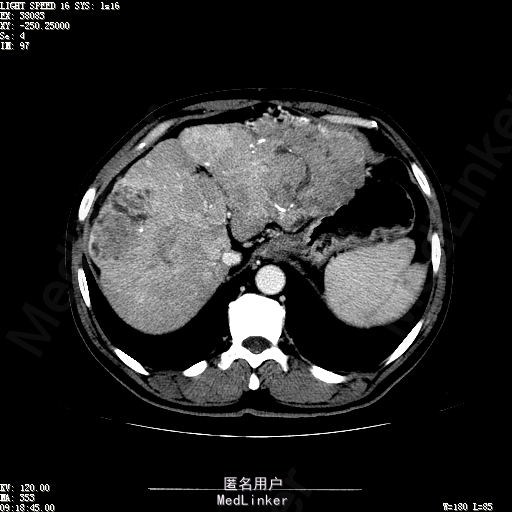

查体:生命体征平稳,神志清晰,发育正常,营养中等,体位自如,表情安静,无面容,配合检查合作。皮肤粘膜颜色正常,腹型平坦,无腹壁静脉曲张,未见胃肠型及蠕动波,无瘢痕,脐部正常。触诊:无压痛,无反跳痛,无腹肌紧张,无腹部包块。肝未触及,Murphy征阴性,脾未触及,肾未触及,无移动性浊音。 化验回报:血细胞分析(五分类):*白细胞计数 4.6 10^9/L、红细胞计数 4.27 10^12/L、血小板计数 100.0 10^9/L、血红蛋白 145 g/L、中性粒细胞百分比 68.6 %,*葡萄糖测定:葡萄糖 5.99 mmol/L,血清离子测定:*钾 4.46 mmol/L、钠 143.5 mmol/L,肾功能检测:*尿素 6.86 mmol/L、肌酐 84.2 umol/L,凝血五项:凝血酶原时间 10.7 秒、凝血酶原百分活动度 93.3 %,乙肝六项:乙型肝炎病毒表面抗原 阳性(+) 、乙型肝炎病毒e抗体 阳性(+) 、乙型肝炎病毒核心抗体 阳性(+) ,甲胎蛋白测定:甲胎蛋白 7146.00 ng/mL,ALT23U/L,AST42U/L CT检查如下图

诊断:乙肝肝硬化 静止性 代偿期 原发性肝癌 2型糖尿病 高血压病 下肢动脉闭塞征 诊断依据:1.有明确乙肝肝硬化病史 2.肝区隐痛,于外院发现肝占位,我院诊断肝癌,已行TACE治疗 3.查体:有肝掌 4.既往影像学提示肝内占位 处置:血管介入治疗:患者平卧位,以左侧肘窝为中心常规消毒、铺巾、利多卡因局麻。超声引导下,于肘横纹上方1厘米处确定皮肤穿刺点,改良Seldinger法逆行穿刺左侧肱动脉成功,置入5F血管鞘。沿导丝送入Cobra C2导管,送入降主动脉,将管头送入腹腔干,进一步送至肝固有动脉。造影见肝内广泛弥漫肿瘤染色,以右叶为主。以微导管超选肝右动脉,造影明确为肿瘤供血动脉,注入碘化油5毫升。退出微导管,经C2管注入奥沙利铂100毫克。退出C2管。拔出血管鞘,局部压迫10分钟。加压包扎。患者送返病房。